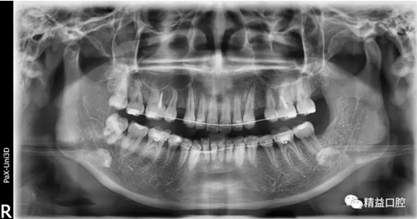

矯正前全口曲斷片

從片子上可以清除看到,上牙門牙牙根吸收非常厲害。

李醫(yī)生考慮到俊上下門牙吸收嚴(yán)重,前牙突度大,建議先拔除上頜兩顆四,對上牙進行內(nèi)收,后期看矯正效果再對下牙進行處理。

為了保證矯正效果和整體牙齒健康,李醫(yī)生在矯正過程中不斷根據(jù)每次牙齒移動的情況,對所施加的矯正力以及每次復(fù)診的時間進行精細(xì)的調(diào)整,在放慢矯正速度的同時,以更加輕柔的力量來拉動牙齒移動。事實證明一切OK,上牙的內(nèi)收效果非常的好。